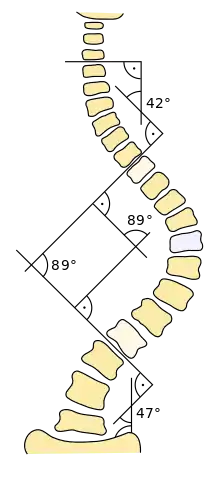

Le principal critère d'évaluation de la scoliose est l'« angle de Cobb », qui se mesure sur une radiographie du rachis de face. C'est l'angle formé à partir de l'intersection de deux droites tangentielles l'une au plateau supérieur de la vertèbre limite supérieure, l'autre au plateau inférieur de la vertèbre limite inférieure. Les conventions médicales veulent qu'un angle inférieur à 10 degrés ne soit pas considéré comme une scoliose à part entière[35]. On peut classer les courbures scoliotiques en fonction de leur importance :

- courbes inférieures à 20 degrés : scolioses bénignes (aucun traitement requis, sauf une surveillance radiologique en période de croissance) ;

- courbes comprises entre 20 et 30 degrés : scolioses moyennes

- courbes supérieures à 30 degrés : scolioses réputées d’emblée évolutives en période de croissance et susceptibles de s’aggraver à l’âge adulte.